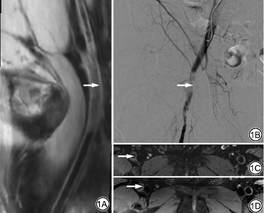

下肢动脉血栓在T1-MATRIX序列上多表现为明显高信号,部分表现为等稍低信号,在T2-MATRIX序列上信号较复杂,部分表现为高信号,部分表现为低信号(图1)。